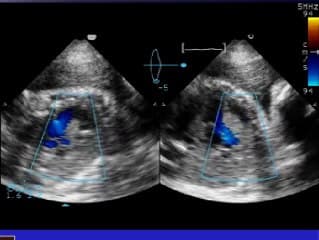

Vous y trouverez des conférences présentées lors des congrès nationaux et internationaux, des cours magistraux dispensés par des experts reconnus, des démonstrations pratiques sur des cas cliniques réels, ainsi que des podcasts et tables rondes sur les dernières avancées de la spécialité.